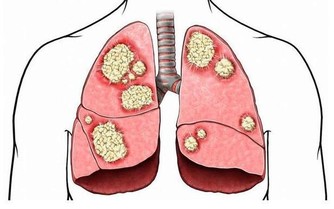

二、胸痛

對於女性來說,乳房的健康狀況一直受到她們的關注,因為乳腺癌是女性的噩夢。所以很多人對於胸部平時會出現的某些疼痛又或者是異樣,都會感覺到十分的恐懼。所以小編今天就來給大家簡單的介紹一下,胸部到底在出現哪些疼痛的時候,是需要我們所關注的。

比如說,有些女性在平時的生活中,胸部有時候會有莫名的脹痛,那麼在這樣的情況之下,就會造成一些女性的恐慌,這是不是代表自己出現了什麼樣的疾病。

其實,胸部有時候會疼痛,只是因為乳腺增生還有就是乳腺炎造成的,所以在這樣的情況之下,只要我們注意平時對它的保養,還有就是去醫院做檢查就可以很好的幫助你排除乳腺癌的風險。

因為早期的乳腺癌患者,她們平時病痛的發病率是比較小的,所以常常沒有什麼樣的疼痛感,直到最後晚期才會出現明顯的刺痛感,還有就是腫痛。這常常是因為乳腺增生,還有就是乳腺瘤壓制導管所造成的。

所以說,女性要想避免乳腺癌的發生,從現在注意就可以了。但是不能過分的在意,因為就像上文中小編說的那樣,有的時候,出現疼痛只是因為乳腺增生等造成的,只要平時注意按摩,還有就是做定期的健康檢查就可以了。

這裡所指的檢查有兩種,一種是進行自我的檢測,平時多關注一些,用手部感知它裡面有沒有出現腫塊等。一旦發現,立刻去醫院就診。還有就是要養成定期做體檢的習慣,因為這樣才全方位的保證你的健康。

結語:以上兩種小編向你們介紹的平時會出現的一些疼痛,只要我們在出現的時候多加的注意,並且在發現異樣時,及時的去醫院救治就可以了。如果你發現了身體出現的一些異樣,但是不進行及時的治療,那麼時間長了之後,再去治療,就會產生無法挽救的後果,影響自己的健康狀況。